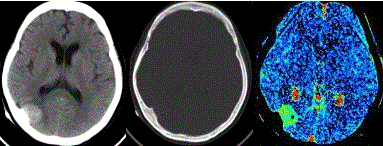

问题 患者女,60岁,头痛半月余。既往体健。腰椎穿刺检查提示脑脊液压力增高。CT及CT灌注表现如下图。 有关该病瘤周水肿的机制,错误的是

选项 A.矢状窦阻塞 B.水肿大小与肿瘤大小无关 C.脑皮质肿瘤细胞浸润 D.肿瘤血供 E.分泌或排泄颗粒

答案 B